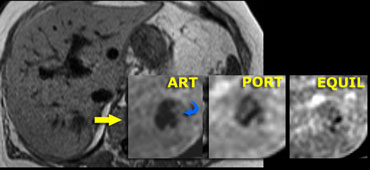

Adenoma: non-specific features on CT Adenoma: non-specific features on CT

Adenoma (3)

On the left an US image of an incidentally found lesion in a 50 y old female.

Work up was done with CT, but only non-specific features were found without signs of hypervascularity. .

Adenoma: capillary blush in arterial phase and signal loss in out of phase image indicating the presence of fat. Adenoma: capillary blush in arterial phase and signal loss in out of phase image indicating the presence of fat.

In contrast to the CT, there clearly is enhancement in the arterial phase on MR, again demonstrating that MR depicts enhancement better than CT.

The enhancement is due to a capillary blush, most intense in the arterial phase with apparent wash-out in portal and equilibrium phase, due to greater enhancement of the surrounding parenchyma.

In the 'out of phase' image there is signal loss indicating that the lesion contains fat, which is very suggestive for adenoma.

A HCC may also contain fat, but in this case there is no cirrhosis and the entire lesion shows signal loss, which we would not expect in HCC.